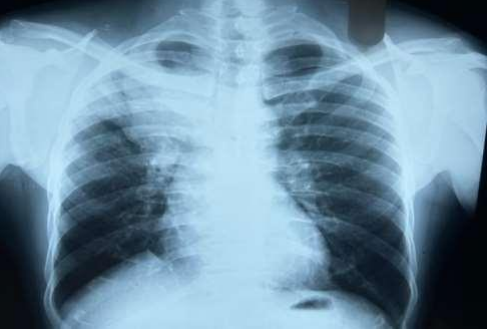

53-year-old male presented to a tertiary care centre elsewhere with complaints of high-grade fever not associated to chills/rigor, productive cough with copious amount of white coloured sputum, breathing difficulty on exertion MMRC Grade III, noisy breathing, chest pain and multiple episodes of haemoptysis. Patient had no other co-morbidities/symptoms of any chronic illness or any other contributary past history. After getting admitted and primary investigations, he was treated with IV antibiotics suspecting pneumonia. After 7 days of treatment patient was referred to our centre as there was no resolution. On clinical examination, patient had shift of trachea to the right side, dullness on percussion, bronchial breath sound and crepitations in the right infraclavicular area. Blood investigations showed leucocytosis (14,000/mm3), elevated levels of ESR (85mm/hr) and CRP (102mg/dl) with no other significant biochemical changes. Chest X-ray taken showed a collapse of the right upper lobe, with the classical ‘Golden S’ sign (figure 1) which raised a suspicion of right upper lobe mass. Further HRCT thorax was taken which showed a ‘bronchial cut off’ sign (figure 2) and an enhancing soft tissue lesion in the right upper lobe with encasement right pulmonary artery and bronchus (figure 3). Patient was taken up for bronchoscopy which showed a right upper lobe mass (figure 4). Bronchial brushings and biopsy (figure 5) were taken and samples were sent for Histopathological study which confirmed Non-Small Cell Carcinoma- Adenocarcinomatous type (figure 6).

Figure 2: CT image showing Bronchial cut-off sign

Figure 3: CT image showing right upper lobe mass

Figure 2

Figure 3